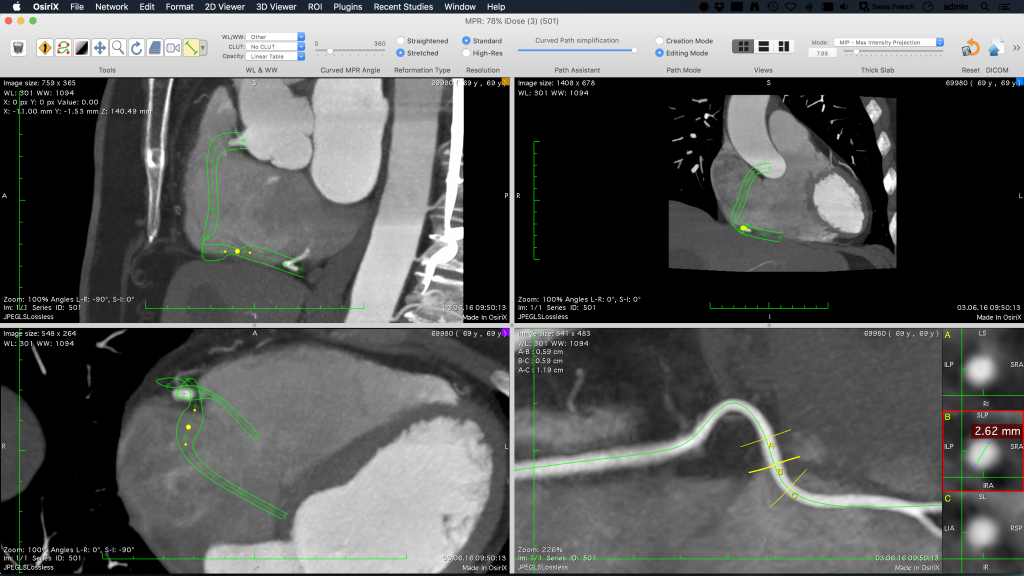

OsiriX MD, MPR (Çok düzlemli Rekonstrüksiyon), 3D Rendering (MIP, Hacim İşleme ve Yüzey İşleme) gibi tüm modern post-processing tekniklerini sunar.

OsiriX MD, aort veya bronşlar gibi organları takip etmek için kavisli düzlemsel rekonstrüksiyonu (3D-MPR) destekler.

3D rekonstrüksiyon görüntülerini film olarak dışa aktarabilir ve PACS’nizde arşivleyebilirsiniz.